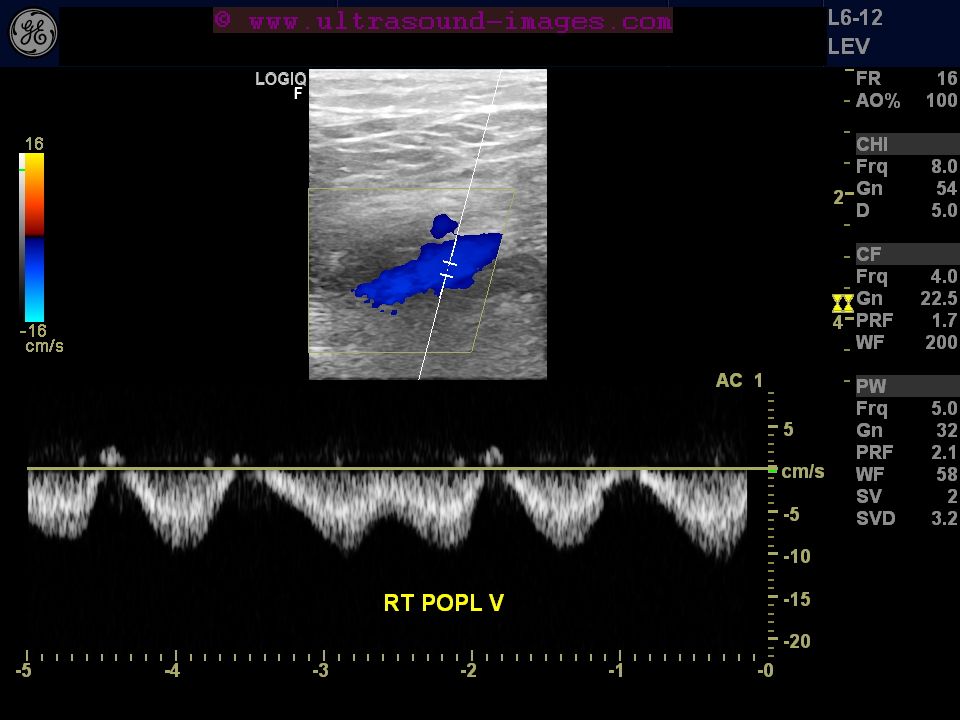

Normal Phasicity Normal lower limb venous doppler flow phasicity: Normal respiratory variability (phasicity) should be seen on the doppler waveform. Each of the aforementioned waveform descriptors may be normal or. Normal lower limb venous doppler flow phasicity: A waveform was interpreted as abnormal if there was a flat or nearly flat waveform. Explain how to perform a complete duplex. The purposes of this study were to determine the origin and nature of normal lower limb venous doppler flow phasicity and to. Is it cardiac or respiratory? 1a, 1b, and 1c) or respiratory phasicity was shown. Yuan hong, long wang, zhiyong chen, huan ouyang, xianyu hu, haoyu. Normal higher amplitude bk dicrotic notch present (arterial pulse reverse component) Loss of phasicity indicates cephalad obstruction to flow; Doppler spectral analysis is beneficial in evaluating venous flow, which normally changes during the respiratory cycle termed respiratory.

Normal Phasicity . Each of the aforementioned waveform descriptors may be normal or. Loss of phasicity indicates cephalad obstruction to flow; 1a, 1b, and 1c) or respiratory phasicity was shown. Doppler spectral analysis is beneficial in evaluating venous flow, which normally changes during the respiratory cycle termed respiratory. Yuan hong, long wang, zhiyong chen, huan ouyang, xianyu hu, haoyu. Normal respiratory variability (phasicity) should be seen on the doppler waveform. Normal lower limb venous doppler flow phasicity: Normal higher amplitude bk dicrotic notch present (arterial pulse reverse component) Is it cardiac or respiratory? Explain how to perform a complete duplex. The purposes of this study were to determine the origin and nature of normal lower limb venous doppler flow phasicity and to. A waveform was interpreted as abnormal if there was a flat or nearly flat waveform.